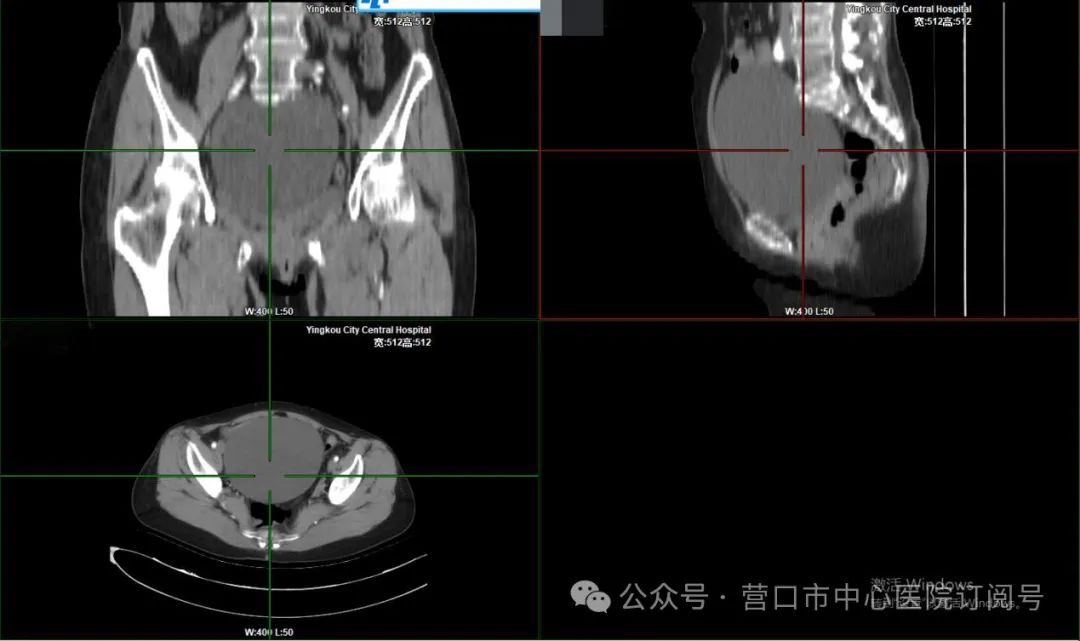

患者女性,61岁,因“绝经后发现盆腔包块1天”就诊于我院,完善盆腔增强CT见盆腔见巨大囊性包块影,较大截面约125x108mm,提示盆腔囊性占位性病变,右侧附件囊肿可能。经过术前评估,排除相关手术禁忌,于单孔腹腔镜下切除右侧附件,患者术后恢复快,术后3天即出院。